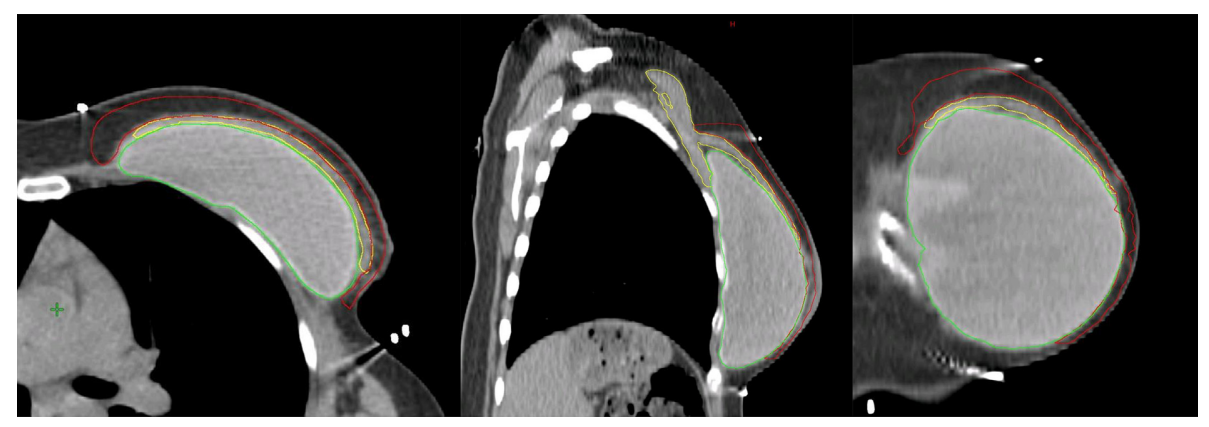

Hình 4a. CTVp_chestwall với chỉ phần trước (Màu đỏ) trong các trường hợp chỉ xạ trị mạng lưới bạch mạch dưới da. Các cơ ngực (Màu vàng) và túi độn (Màu xanh).

Nếu mạc sau tuyến vú không bị xâm lấn bởi ung thư, CTVp_chestwall cho PMRT không bao gồm mạng lưới bạch huyết sâu, do đó, chỉ bao gồm viền tổ chức mô phía trước cơ ngực lớn và túi độn, ngoại trừ ở phía trong, ngoài và dưới, nơi CTV có thể được mở rộng để bao phủ phần thành ngực không được bao phủ bởi cơ ngực lớn trước mổ. Như vậy, phần lớn túi độn có thể được loại khỏi CTVp_chestwall, trong khi các phần thành ngực xung quanh cơ ngực với các dòng chảy bạch huyết vẫn nên được bao phủ. (Hình 4a, b). Lớp cơ ngực phía trên túi độn có thể rất mỏng ở một số người bệnh, vì vậy, thể tích bia lâm sàng thường khó tránh khỏi phải bao gồm ít nhất một phần cơ ngực, nghĩa là giới hạn sau của CTV sẽ là bình diện trước của túi độn.